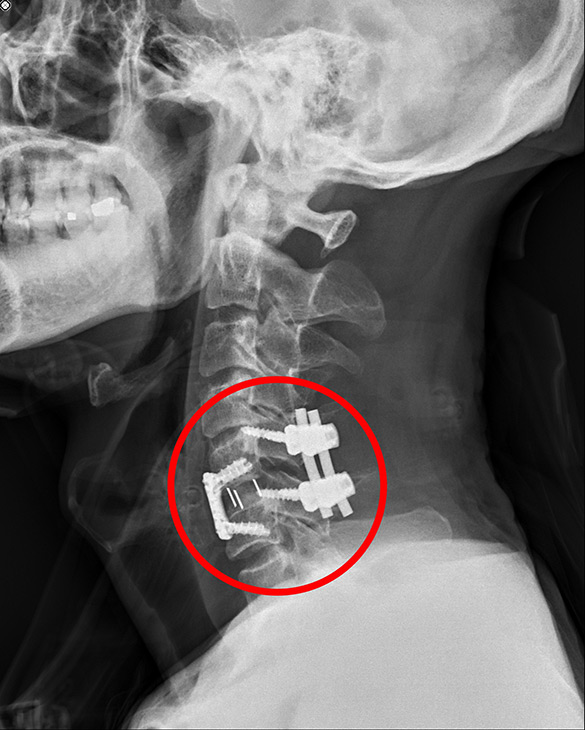

洪祥益主任五個小時內為宋先生進行三階段手術,一是先將頸椎骨折脫臼復位,接下來以顯微鏡清除壓迫到神經的破碎椎間盤和骨刺後再融合,最後在頸椎後方以四根釘子做後固定加強,等於頸椎前後做了三百六十度的固定融合手術。